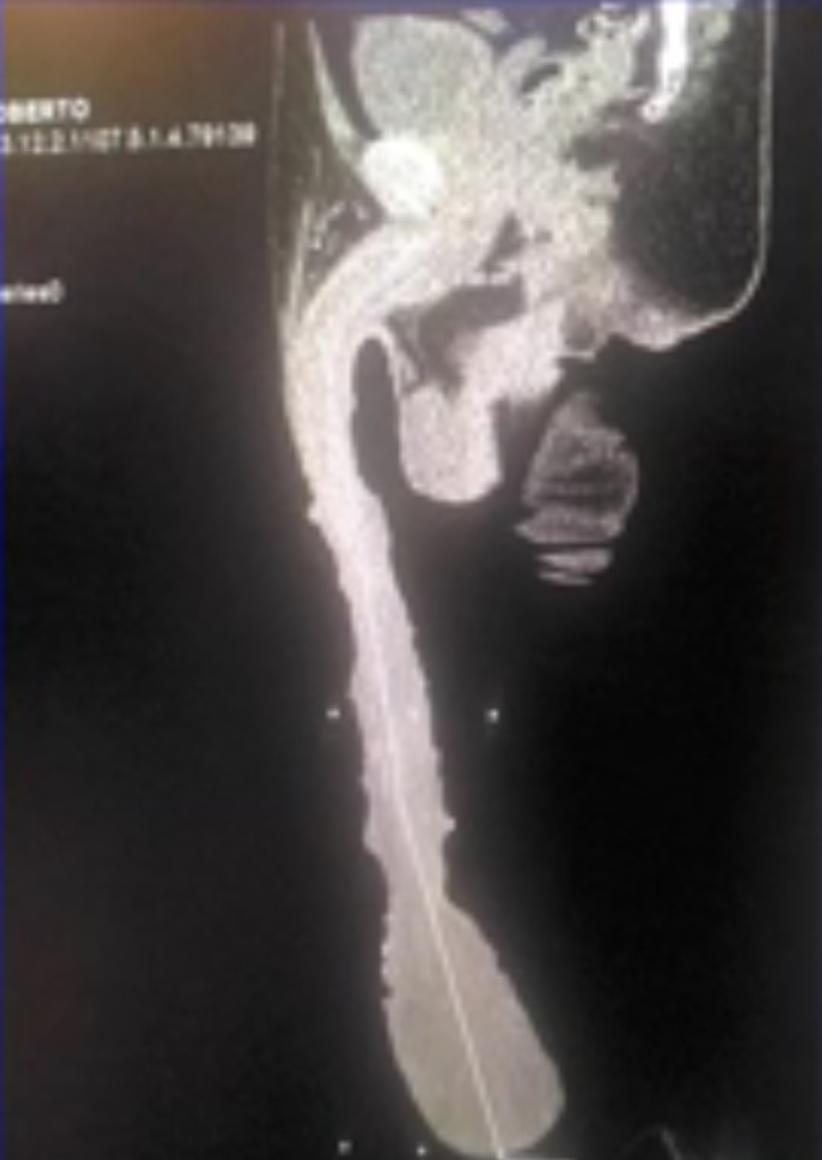

Roberto Esquivel Cabrera, de 52 anos, quer entrar para o Guiness Book por ter o maior pênis do mundo.

Com 48 cm de comprimento, o membro é tão longo que vai abaixo do joelho impossibilitando o mexicano de fazer coisas básicas como ajoelhar na missa, por exemplo.